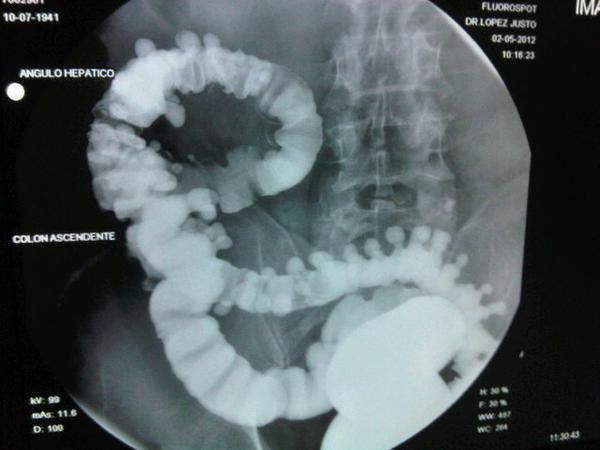

Los tipos especiales de exámenes de rayos X llamados estudios de contraste utilizan tintes con base de yodo o materiales de contraste, como el bario, junto con las radiografías para que los órganos aparezcan en la radiografía y obtener mejores imágenes. Por ejemplo, las radiografías del tracto gastrointestinal inferior, normalmente llamado examen de enema de bario, se emplean para tomar imágenes después de que el intestino se llena con sulfato de bario. Otro estudio, un pielograma intravenoso, usa un colorante especial para examinar la estructura y el funcionamiento del sistema urinario (uréteres, vejiga y riñones).

Radiografías del tracto gastrointestinal inferior (enema de bario): se puede restringir su alimentación durante algunos días antes del estudio. Se usan laxantes, enemas, o ambos, para vaciar el intestino grueso. Para el estudio, usted se acuesta y será sujetado a una mesa. Se toma una serie de radiografías. Luego el líquido de bario se coloca dentro del intestino por medio de un tubo pequeño y blando ubicado en el recto. El líquido se siente frío. Se procede a tomar más imágenes mientras la mesa le inclina a usted en diferentes posiciones. Esto ayuda a que el bario se mueva por los intestinos de modo que puedan verse en las radiografías. Tiene que permanecer acostado inmóvil y contener la respiración cuando se toma cada imagen.

Para obtener imágenes más claras, por lo general se realiza un examen con “contraste doble”. En este examen se usa una cantidad más pequeña de líquido de bario más espeso. Después que el bario está adentro, se hace ingresar aire en sus intestinos. Esto puede causar una sensación de hinchazón y malestar, junto con la ganas de vaciar los intestinos.